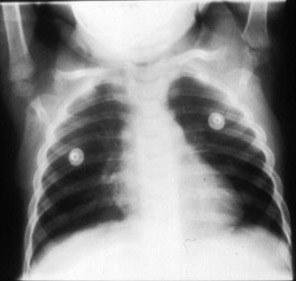

Inspiratory film